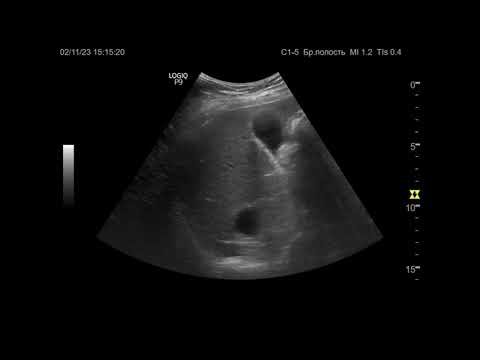

УЗИ. Доктор Иогансен. Выпуск 20. Эхинококковые поражения печени. Часть 2.

Вторая часть изложения темы "Эхинококковые поражения печени". Представлены ультразвуковые признаки эхинококковых кист печени и их классификации. Ссылка на Дзен: Ссылка на RuTube: